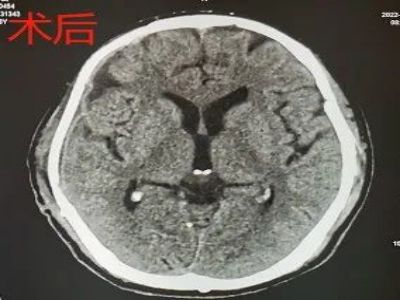

杨先生不慎从工地高处坠落,被紧急送至当地医院,入院后行头胸CT检查,提示右侧额颞顶脑挫伤伴硬膜下出血,蛛网膜下腔出血,枕骨骨折,左锁骨骨折,左肩胛骨骨折,左侧多肋骨骨折,胸椎横突骨折。因病情危重,在经过一系列抢救后,被送入了ICU病房。

入院诊断:颅内损伤 硬膜外血肿 脑术后 颅骨缺损 肺部感染 枕骨骨折 左锁骨骨折 左肩胛骨骨折 左多肋骨骨折 胸椎横突骨折 头皮裂伤 心包积液 胸腔积液 脂肪肝

应家属要求,完善术前检查后,行“右侧颅骨修补术”。